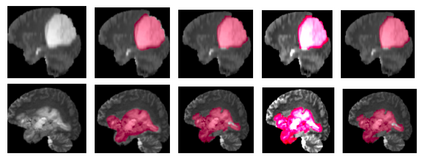

Deep learning motivated by convolutional neural networks has been highly successful in a range of medical imaging problems like image classification, image segmentation, image synthesis etc. However for validation and interpretability, not only do we need the predictions made by the model but also how confident it is while making those predictions. This is important in safety critical applications for the people to accept it. In this work, we used an encoder decoder architecture based on variational inference techniques for segmenting brain tumour images. We evaluate our work on the publicly available BRATS dataset using Dice Similarity Coefficient (DSC) and Intersection Over Union (IOU) as the evaluation metrics. Our model is able to segment brain tumours while taking into account both aleatoric uncertainty and epistemic uncertainty in a principled bayesian manner.